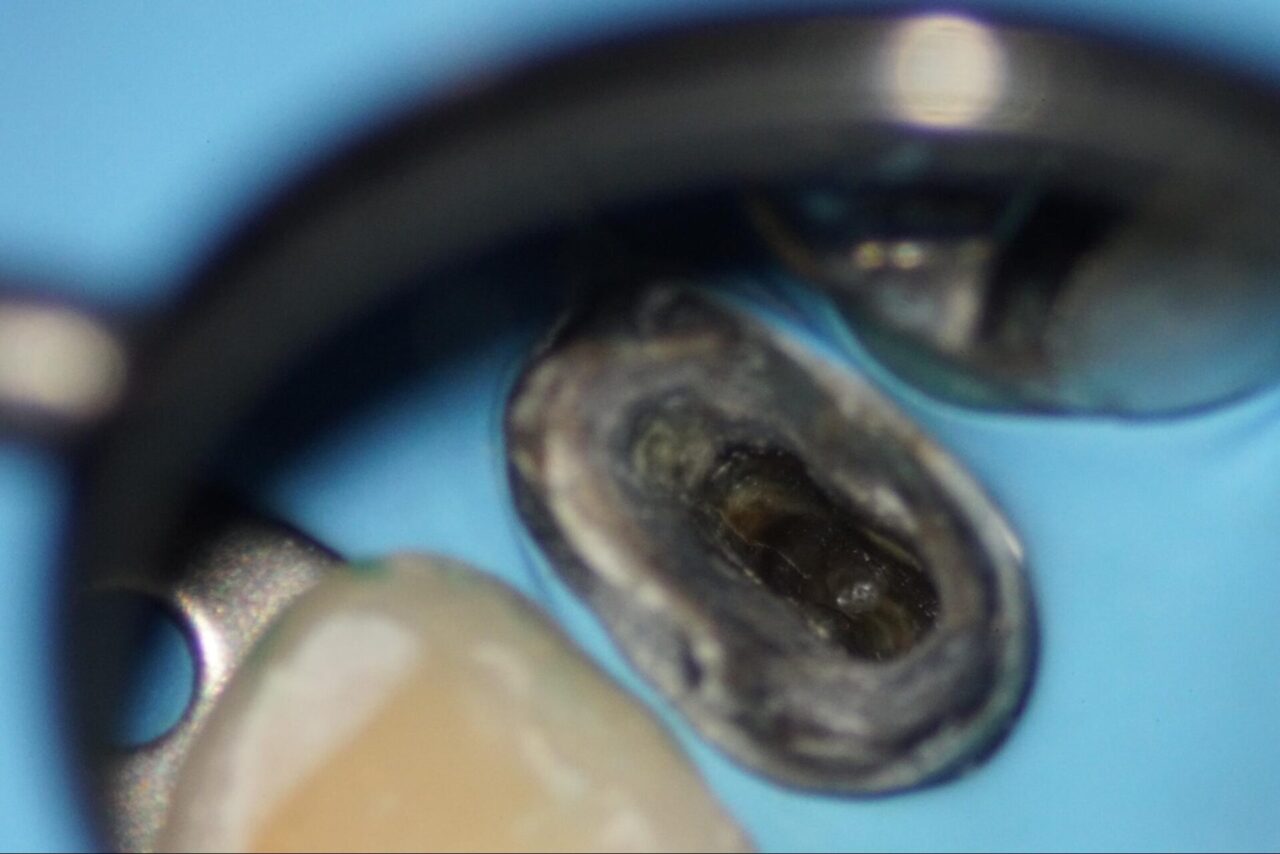

なぜ破れたのか?の原因除去を行わなければ、また短期間で破れてしまいます。

最終的なレーザー洗浄を行い、根管充填を行いました。

バイオセラミックによる根管充填を行いました。

歯冠形態を作って初日は終了です。